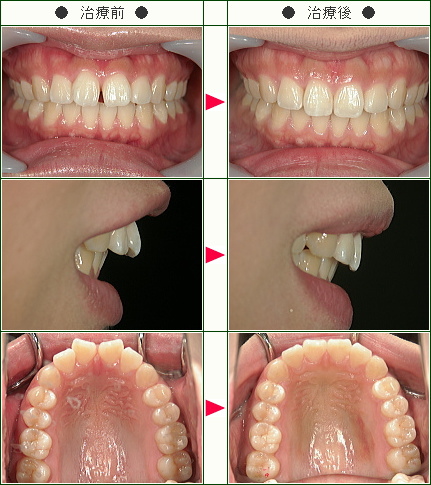

☆前歯のすきっ歯矯正症例[T.N様 35歳 男性]